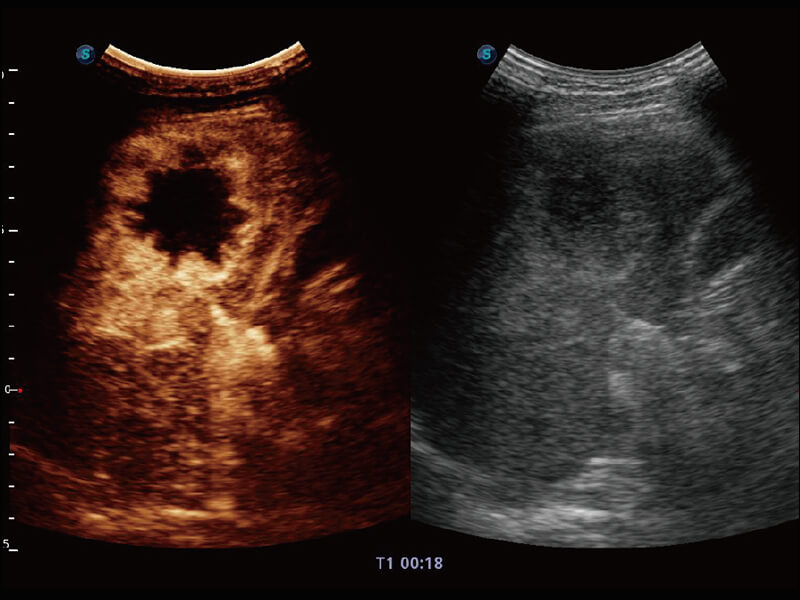

成像功能

S60探头工艺,从前端信号处理每一个环节采集无损声学数据,真实还原组织原貌,再现解剖细节。

超宽频带技术,为容积成像带来优质的二维图像基础,为您呈现丰富的结构细节,栩栩如生地展示宝宝的宫内形态以及各种组织的立体结构。